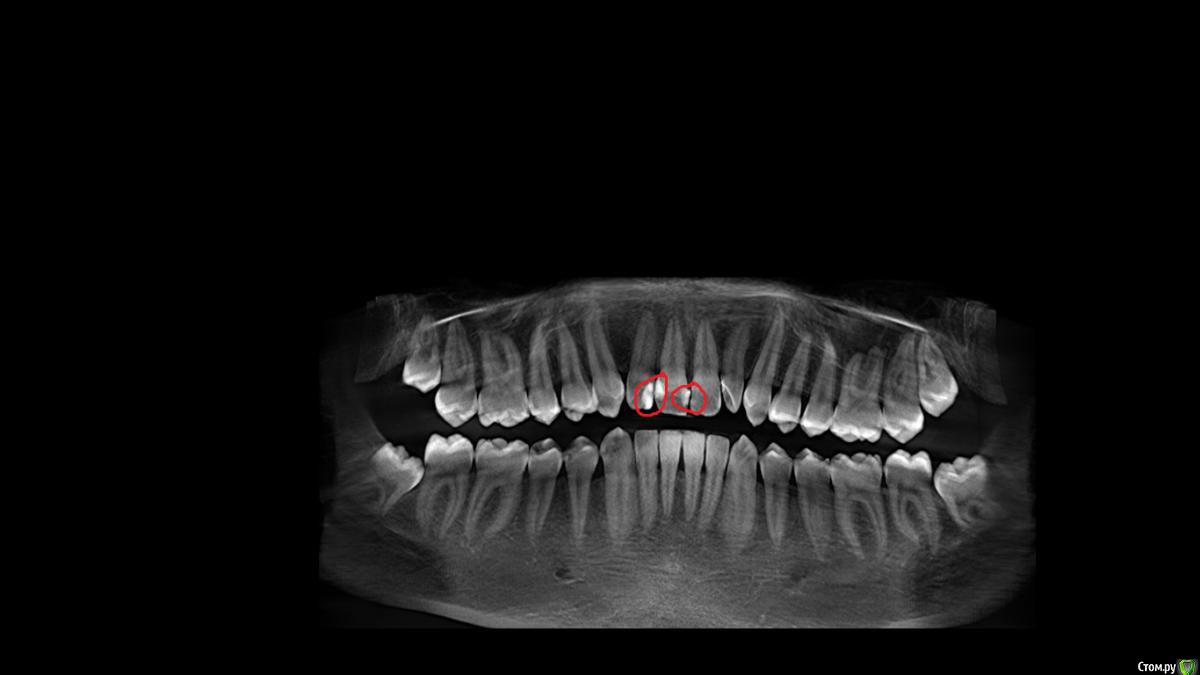

Виктор1995 Опубликовано 1 апреля, 2016 Поделиться Опубликовано 1 апреля, 2016 Такой вопрос. Решился сходить к стоматологу после 2 лет перерыва (идиот да ), так как немного воспалились десны и иногда чуть чуть кровоточат, чувствительности почти никакой. Читал что это все от зубного налета ( камня ) в основном , называется гингивит и тд? Прошла консультация и я просто испугался. У меня где десны воспалены , передние зубы, там стоят пломбы, старые и да она сказала что их края уже во все стороны разбегаются , плохое состояние и надо в общем менять. У меня они довольно большие , я в принципе был согласен , но потом она стала говорить что нужно сделать 3D томограмму для точности , и вдруг там под пломбами пошел кариес или еще что то ,не помню , тогда надо будет еще и удалять нерв. Естественное она сказала не точно. Я просто блин задрожал, у меня не было зубной боли и я пришел лишь по причине небольшого воспаления десен. Прочитал много инфы с разных сайтов.Зуб становится мертвым и чернеет, Болезнь называется пульпит ? У меня нет никакой боли, стоят 2 пломбы на месте воспалившийся десны, старые. Причина воспаления десен может быть в них ? Они воспалились примерно месяц назад. Согласился на проф чистку всей полости рта (зубной камень , налеты и тд) и на след день 3d томограмма .Что делать если она скажет что действительно нужно удалять нерв? Соглашаться или искать другую клинику? Мне всего 21 год и это передние зубы, очень боюсь этого, даже таких неточных слов , я думал десна воспалились от зубного камня. Написал как мог, надеюсь читабельно. Любые деньги сейчас готов отдать , лишь бы без удаления нерва , хотя ещё до 3D , ничего не ясно. На прилогаемой картинке вот 2 покраснения, все насчет левого. Заранее спасибо. http://s014.radikal.ru/i327/1604/2d/a0e1c0a1af30.jpg Ссылка на комментарий

St. Опубликовано 2 апреля, 2016 Поделиться Опубликовано 2 апреля, 2016 Десна может воспаляться по разным причинам, в том числе и от плохой гигиены(т.е. остатков пищи и образовавшегося камня), и от шероховатых нависающих краев пломб (потому что там задерживается налет). Выложите сначала панорамный снимок, в КТ сейчас особой необходимости не вижу. Прочитал много инфы с разных сайтов.Зуб становится мертвым и чернеет, Болезнь называется пульпит ? У меня нет никакой боли, стоят 2 пломбы на месте воспалившийся десны, старые. Да, воспаление нерва в зубе называется пульпит. Зуб темнее не всегда, и даже не всегда может болеть. По снимкам мы предполагаем возможное воспаление нерва если пломба большая и глубокая. Сказать же однозначно можно только убрав старые пломбы и посмотрев что под ними. Ссылка на комментарий

Виктор1995 Опубликовано 3 апреля, 2016 Автор Поделиться Опубликовано 3 апреля, 2016 Сделали мне КТ. С нервом слава Богу все обошлось. Сказали нужно менять 3 старые пломбы так как именно они влияют на покраснения десны, их края. У меня вопрос, каким материалом лучше.? Световые пломбы либо жидкие (Icon да?) или жидкие в данной ситуации не подойдут так как тут довольно большая часть зубов затронута ( по крайней мере что слева на снимке КТ) или на передние не делают? Сказали не беспокоят ли восьмерки , никаких болезненных ощущений нет у меня пока, вообще. Сказали стараться не медлить с этим, это уже на будущее. Я из СПБ , вот заранее спасибо за ответы если кто что посоветует ! Ссылка на комментарий